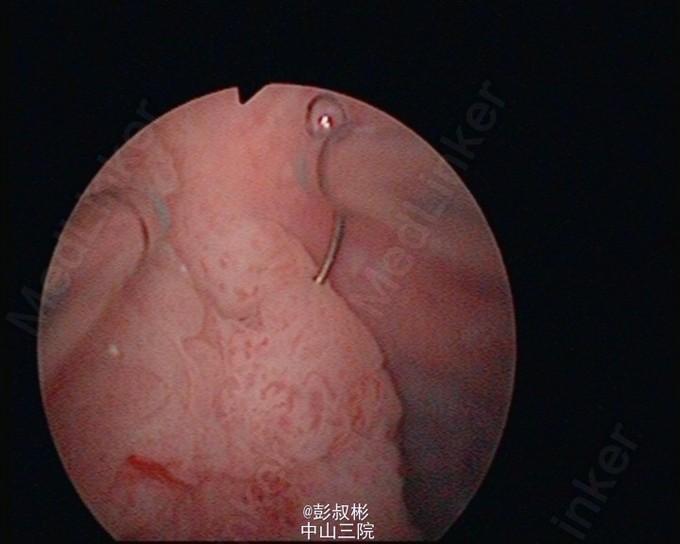

膀胱肿瘤电切实录--看看膀胱癌长这样

主诉 病史

68岁,男性,反复肉眼血尿3个月。盆腔CT:膀胱左前下侧壁约20×21×21 mm肿块,考虑膀胱癌可能性大。术前诊断:膀胱癌。患者合并心肺功能不全,要求保留膀胱。